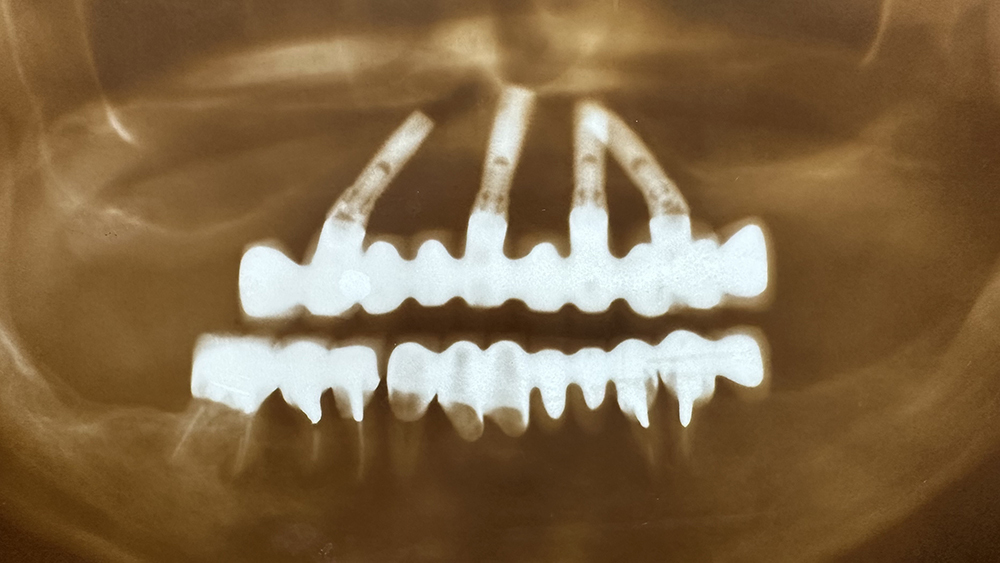

症例1

非喫煙、碧南の陶芸家 70代男性

治療の期間・回数:①約7か月 ②約8か月 ③5か月

治療の価格:①2,200,000円 ②約8,000,000円 ③約300,000円

治療内容:この方は平成22年に初めて来院されました。

①他院で下あごの奥歯にインプラント治療を受けていましたが、上あごは「できない」と言われたそうです。当院では上あごに7本のインプラントを入れ、その日のうちに仮のブリッジを装着しました(即時荷重)。

②令和元年には、左上の奥のインプラントが抜けてしまったため、骨を足す手術(サイナスリフト)を行い、同時に2本のインプラントを追加しました。その半年後に、以前のブリッジを修理して再利用しています。

③さらに令和3年には右下の奥歯が折れてしまったため、インプラントを1本追加しました。当院では再治療や追加治療の場合、費用は2割引きとしています。

現在、上あごのブリッジは「コバルトクロム合金+セラミック」で作られた、スクリューでしっかり固定するタイプです。精度が高く、長く安定させるために、このような固定方法が望ましいと考えています。